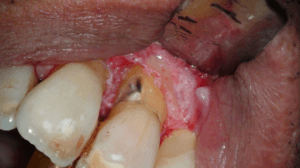

Na het wegfrezen van het losse stukje vulden we het defect op met composiet. We werken de composiet af met fijne diamantjes en handscalers. Een superscherp geslepen handinstrument kan uitstekend worden gebruikt bij het afwerken van composietvullingen. Wel alleen vlak na het polymeriseren, dan is composiet nog te scalen.

Na polijsten hechtten we de flap en maakten we een afspraak voor een week later.

Na 6 maanden

Toen we de patiënt terug zagen na drie maanden was het aspect van de 11 weer gezond. De pocket was gereduceerd, er was geen pusafvloed meer en het tandvlees zag er gezond uit.

Achteraf analyserend kunnen we stellen dat de situatie niet ideaal is. Er is een composietrestauratie gemaakt in het meest kwetsbare deel van het element en de restauratie ligt gedeeltelijk nog onder de gingiva. We hopen dat het lang goed gaat maar lekkage ligt op de loer natuurlijk en wellicht is het nodig om na een aantal jaren opnieuw een flapje te doen en de restauratie te vernieuwen.